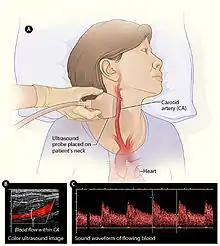

Angiology (vascular)

In angiology or vascular medicine, duplex ultrasound (B Mode imaging combined with Doppler flow measurement) is used to diagnose arterial and venous disease. This is particularly important in potential neurologic problems, where carotid ultrasound is commonly used for assessing blood flow and potential or suspected stenosis in the carotid arteries, while transcranial Doppler is used for imaging flow in the intracerebral arteries.